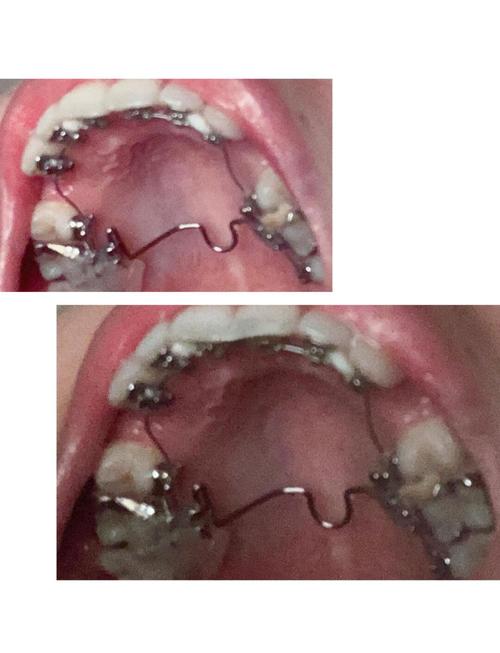

在正畸项目设置上,沈河牙病防治所涵盖了多种主流矫正方式,以满足不同患者的需求,针对青少年常见的牙列拥挤、龅牙、地包天(反颌)、开颌等问题,提供传统金属托槽矫正、陶瓷半隐形矫正,兼顾矫正效果与性价比;对于注重美观的成年患者,则有隐形矫正(如时代天使、隐适美等品牌)和舌侧矫正,其中隐形矫正因美观、舒适、可摘戴的特点,成为职场人士的热门选择,舌侧矫正则完全隐藏于牙齿内侧,实现“隐形”矫正效果,该所还开展儿童早期矫治,针对替牙期出现的功能性错颌(如不良习惯导致的颌骨发育异常)进行干预,降低后期正畸难度。

正畸治疗是一个系统化的过程,通常包括以下几个阶段:初诊检查阶段,医生会通过口腔检查、X光片(曲面断层片、头颅侧位片)、取模或口扫等方式,全面评估患者的牙齿、颌骨、面部软组织情况;方案设计阶段,结合检查结果与患者需求,制定详细的治疗计划,包括矫正方式选择、治疗周期、预期效果等,并与患者充分沟通确认;矫治器佩戴阶段,根据方案制作或定制矫治器,医生进行专业粘接或佩戴指导;复诊调整阶段,按照约定时间定期复诊(通常1-1.5个月一次),医生会检查牙齿移动情况,调整矫治力或更换隐形牙套;保持阶段,拆除矫治器后需佩戴保持器(通常建议夜间佩戴至少2年),防止牙齿复发。